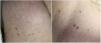

As a result of her disease relapse, the patient was planned for admission to receive the natural killer cell therapy in a clinical trial. Two weeks before admission (T+356), she had a COVID-19 interview screen prior to a routine clinical appointment. Such screening is now standard for all patients entering our institution. At the time, she reported vigilant social distancing and no respiratory symptoms. A review of systems was notable for chronic intermittent diarrhea and a week-long history of a pruritic skin rash; both were distinct from her prior GVHD symptoms. She was otherwise well, with no respiratory symptoms. Upon examination, her temperature was 37.3°C and oxygen saturation was 99%. The examination of her skin revealed pink erythematous patches on her trunk (Figure 1). The laboratory evaluation demonstrated stable pancytopenia, without neutropenia or lymphopenia. The skin biopsy from her right back to rule out GVHD demonstrated a very mild superficial perivascular lymphocytic infiltrate, without notable eosinophils, and a mild perifollicular lymphocytic infiltrate with parakeratosis overlying follicles (Figure 2). The histologic findings were suggestive of a viral exanthem. During the pre-appointing screening, she did not meet institutional criteria for the SARS-CoV-2 testing at the time of biopsy, in part due to triage algorithms designed to conserve available test kits. Her therapeutic plan included clinical trial enrollment and a plan to admit for conditioning chemotherapy in two weeks.

A day before her planned admission (T+370), she received the COVID-19 testing per the newly implemented policy and had a positive test for SARS-CoV-2. She was afebrile with no new symptoms and reported improvement, but not resolution, of her rash. Her chemotherapy was therefore postponed and the patient started two weeks of home isolation with remote interactions. Two weeks later (T+384), she continued to report no respiratory symptoms and reported no further diarrhea. Upon examination, she was afebrile and again and found to have complete resolution of the rash. Two SARS-CoV-2 PCR tests on T+384 and T+385 were negative and she was ready to proceed with the planned procedure.